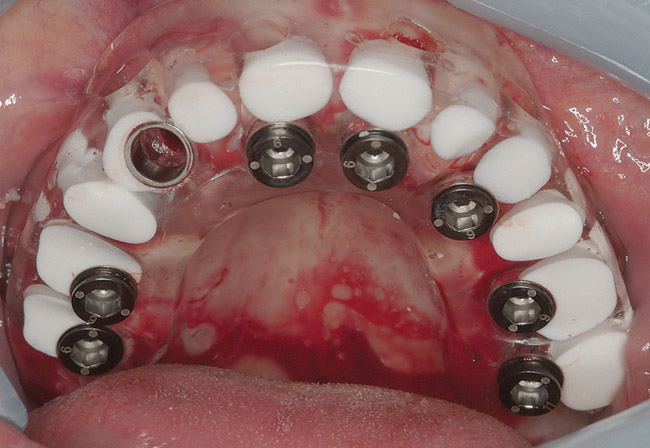

Figure 18  Flapless, computer-guided implant insertion.

Figure 18

Figure 19  Removal of surgical guide enabled inspection of implant placements.

Figure 19

The patient was scanned with a cone beam CT scan while wearing a radiopaque scanning appliance based on her new treatment denture. Horizontal bone augmentation was confirmed radiographically, and both grafted sinuses resulted in satisfactory bone quantity for implant placement. Vertical augmentation was not attempted because of the patient’s unwillingness to forego her removable prosthesis for any period of time. Therefore, shorter implants were treatment-planned, resulting in the placement of eight implants, rather than fewer—such as six—implants, to support a full-arch fixed prosthesis. Because adequate bone and keratinized mucosa were present, a flapless, computer-guided implant insertion was performed (Figure 18). After removal of the surgical guide, placement of all eight implants could be inspected (Figure 19). Post-placement periapical radiographs are shown in Figure 20 and Figure 21.